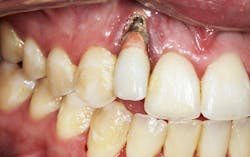

- Thinning of the hard and soft tissues around the dental implant (figure 2), which can increase the risk of a failed implant if tissue support is compromised

- Changes in occlusal patterns and force distribution, leading to possible fracturing of the implant components (figure 2a). Such changes can increase the risk of a failed implant and may require additional implant treatment to restore function and stability.